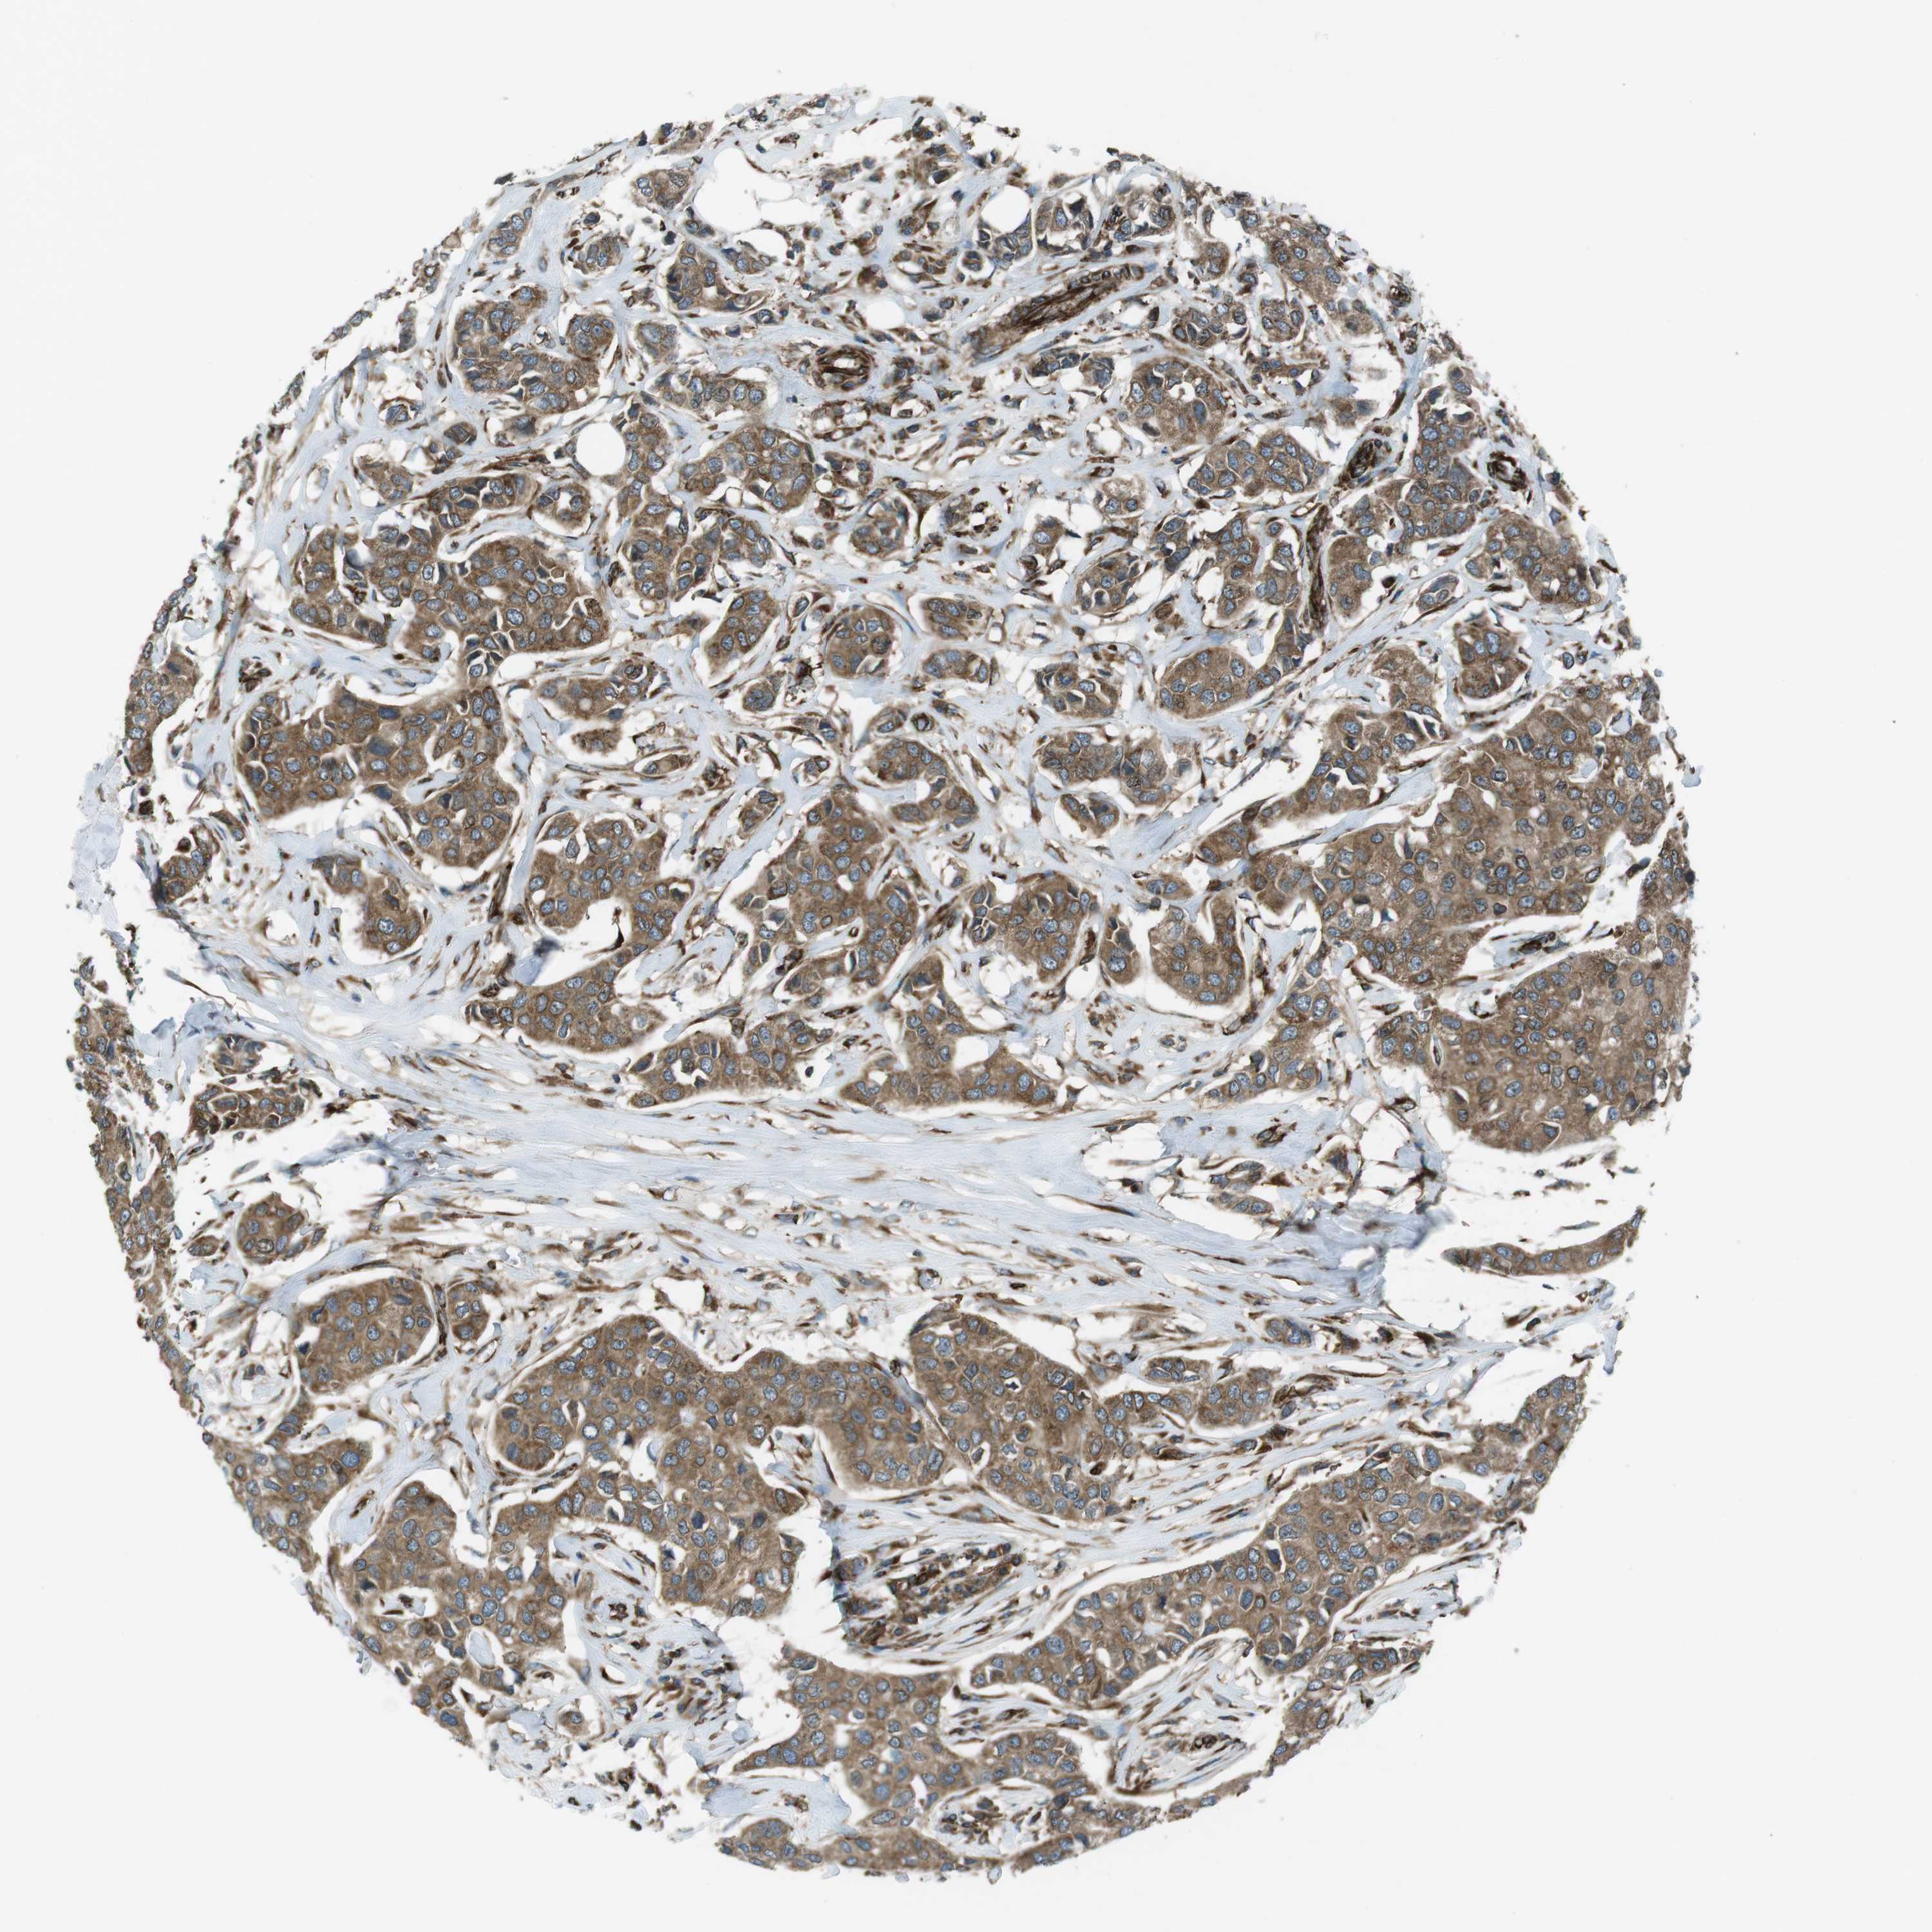

CANCER BREAST CANCER Show tissue menu

BRCA TCGA BRCA VALIDATION PROTEIN EXPRESSION